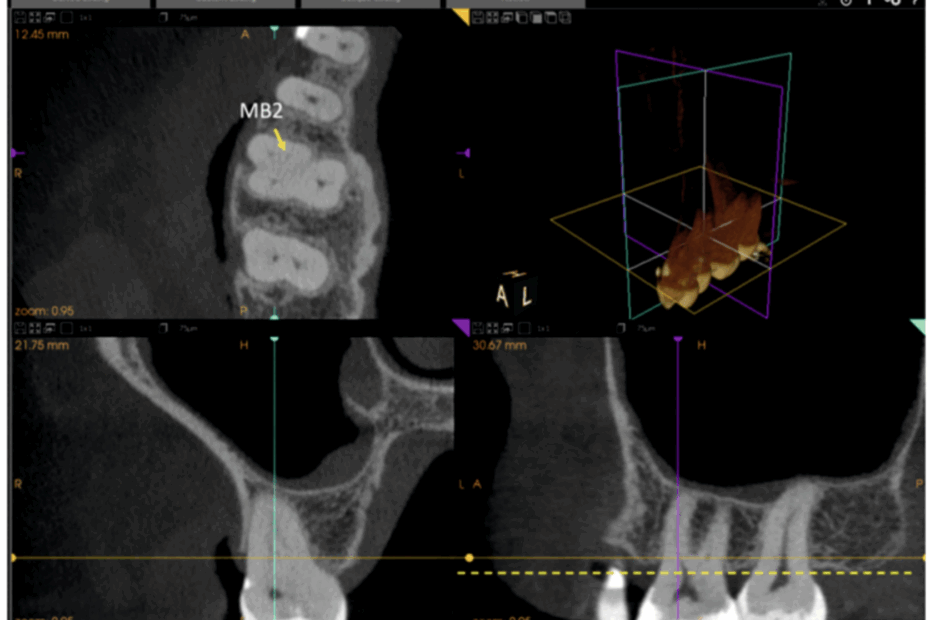

A importância da Tomografia Cone Beam na análise tridimensional do segundo canal mesiovestibular (MV2)

A tomografia cone beam em odontologia revolucionou o modo como avaliamos a anatomia interna dos dentes, especialmente nos molares superiores, onde a presença de canais acessórios pode comprometer o sucesso do tratamento endodôntico. Entre eles,… A importância da Tomografia Cone Beam na análise tridimensional do segundo canal mesiovestibular (MV2)